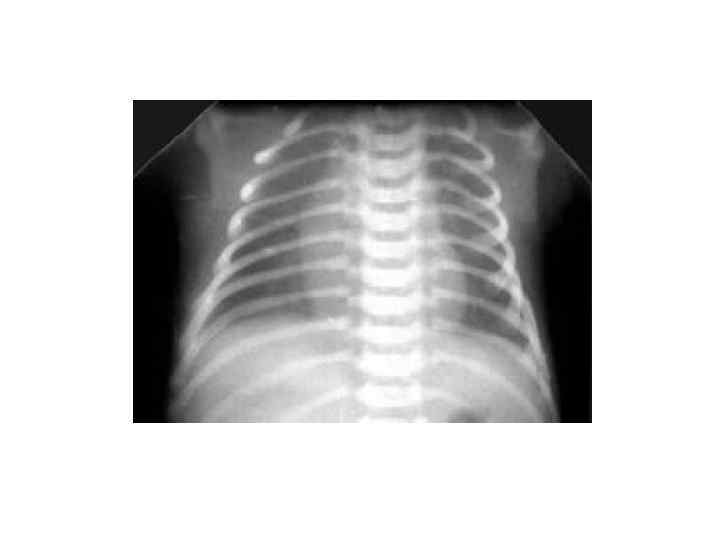

Диагностика § Анамнез § Клиническая картина § Данные рентгенологического исследования грудной клетки Рентгенологическая картина, характерная для БГМ: § Диффузные симметричные очаги пониженной прозрачности (симптом «матового стекла» без или с признаками «сетчатых легких» ) § Воздушная бронхограмма § Пониженная пневматизация периферических легочных полей

Диссеминированные, рассеянные ателектазы: § У незрелых глубоконедоношенных детей § Генез – дефицит сурфактанта и плохое расправление артериол легких § Клиника: - ДН с рождения, - перкуторно - мозаичное укорочение звука, - аускультация - ослабление дыхания, незвучные, крепитирующие хрипы § Рентгенологически – рассеянные очаги уплотнения и участки викарной эмфиземы Течение ателектазов – 3 -5 дней, если не наслаивается бактериальная инфекция.